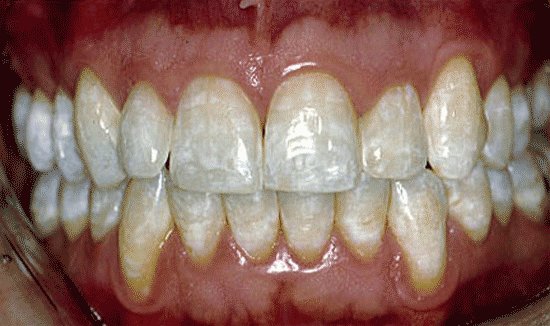

В норме зубная эмаль блестящая, гладкая. При флюорозе эмаль на пораженных участках тускнеет и белеет, становится словно мел. В дальнейшем эти участки могут накапливать пигмент и окрашиваться в желтый, коричневый цвет.

Меловидно-крапчатая форма

Для этой формы флюороза свойственны различные проявления. Зачастую эмаль на всех зубах становится матовой, а на ее поверхности визуализируются пигментированные пятна. В других случаях эмаль становится желтой и покрывается точками, пятнами. Иногда на поверхности зуба формируются даже крапинки с убылью эмали в глубину. Дно таких точечных образований окрашивается в желтый, коричневый цвет.